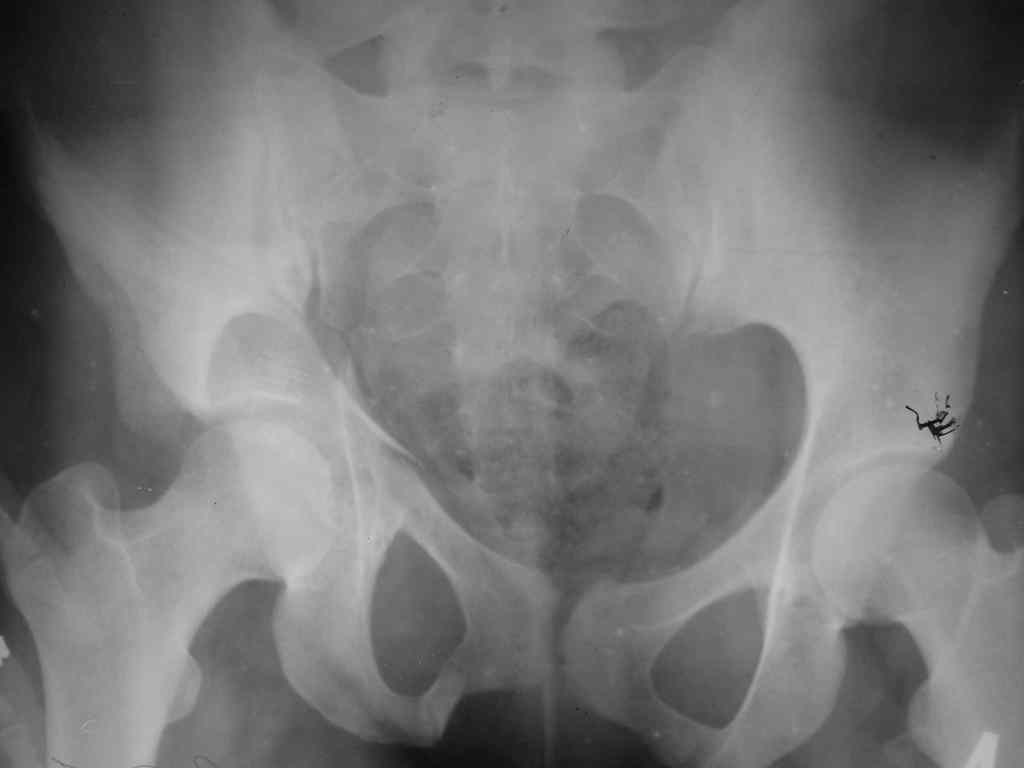

Здравствуйте, коллеги! 27/01/07 в отделение поступила девушка с множественным переломом костей таза справа с нарушением тазового кольца, ротационная нестабильность (седалищная, лонная кости, крыло подвздошной кости, перелом дна вертлужной впадины) и закрытый перелом обеих костей голени справа. При поступлении наложена система скелетного вытяжения за пяточную кость справа. Проведена противошоковая терапия. Состояние в данный момент стабильное. Планируется оперативное лечение перелома костей голени в наших условиях и наложение системы скелетного вытяжения за правое бедро на этой неделе. Просим рассмотреть вариант оперативного лечения травмы таза в условиях УНИИТО.

Здравствуйте, коллеги. У больной имеется высокий двухколонный перелом. Суставная поверхность скорее всего разошлась не сильно (Сделайте запирательную проекцию). Смущает обратная клиновидность щели сустава и укорочение при молодом возрасте.